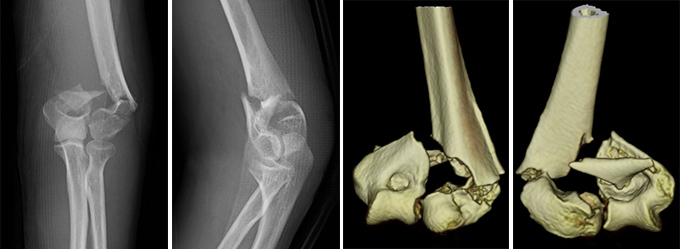

肘関節脱臼骨折(OFD・PLRI・PMRI・TTI)

脱臼に骨折や靱帯損傷を伴う複合的な肘外傷で、治療が難しい重症な外傷です。代表的なものに、肘頭脱臼骨折(OFD)、後外側回旋不安定症(PLRI)、後内側回旋不安定症(PMRI)、橈骨頭と鉤状突起骨折を伴うテリブルトライアッド(TTI)などがあります。これらは骨折と靱帯損傷の双方を正確に整復・修復しなければ、慢性的な不安定性や痛み、可動域制限を残す可能性が高いです。近年は治療戦略が構築されてきており、プレート固定やアンカーなどを用いた靱帯縫合により、安定した関節機能の再獲得が可能となってきています。

症例① 60代 女性

症例② 40代 男性